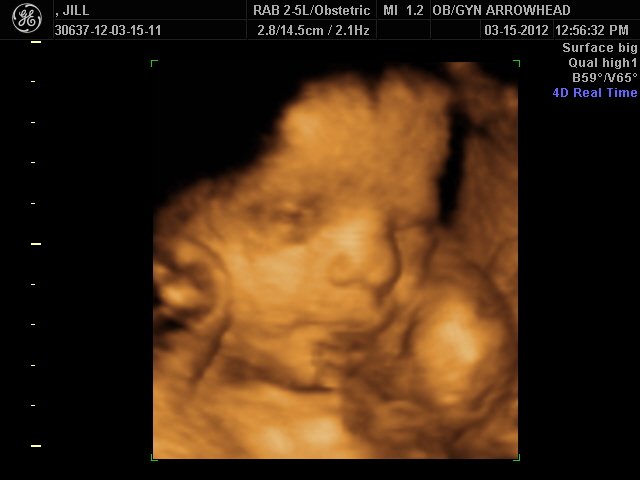

We offer complimentary 3D/4D Ultrasounds to all our OB patients around 30 weeks! The following photos are some examples of our work, shown with permission from our patients.